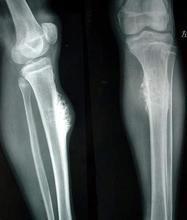

骨腫瘤的診斷有的比較容易,單憑臨床檢查即可作出初步診斷,如表淺部位的骨瘤或骨軟骨瘤等,有的在x線片上有特點,可根據典型的x線所見得出初步印象如硬化性骨肉瘤、軟骨肉瘤等;有的則須結合臨床、x線和病理,綜合分析,才能作出正確診斷。因此,臨床、x線和病理被認為是診斷骨腫瘤的三個重要步驟,有時是缺一不可的。尤其在考慮採用截除肢體的手術之前,一般都要經過上述三方面的檢查確診,才能決定。

(四)x線所見:良性骨腫瘤的界限多比較清楚,與正常骨質之間常有明確的分界線,一般無骨膜反應,如有反應,骨膜新骨也比較規則、整齊。惡性骨瘤則邊界不清楚,與正常骨質之間分界不清,骨膜反應紊亂,甚至形成日光放射狀。